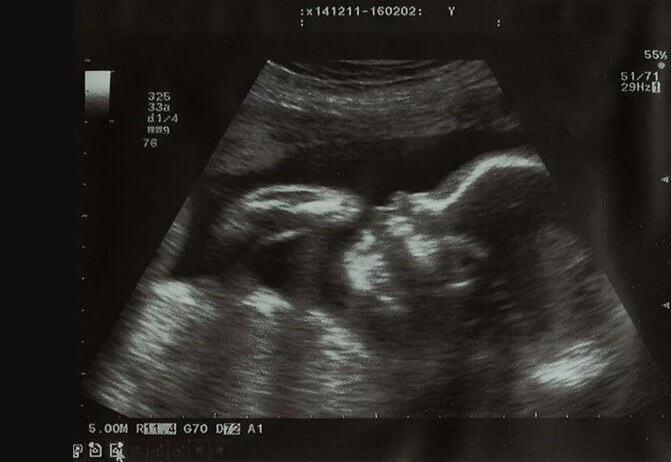

24 Haftalık Bebeğin Ultrason Görüntüsü

Bebeğinizin ultrason görüntüsünün diğer 24. haftasındaki bebeklere benzememesi sizi endişelendirmesin; çünkü ultrasın görüntüleri günün saatlerine göre bile değişebilmektedir ve her bebeğin anne karnındaki gelişimi kendine özeldir.

• Bebeğinizin minik parmakları bu haftalarda hızlıca gelişmeye devam ettiği için bebeğinizi küçük ellerini yummaya çalışırken görebilirsiniz.

• Hatta bebeğinizi göbek kordonu avucunda mışıl mışıl uyuyorken görme ihtimaliniz bile var.